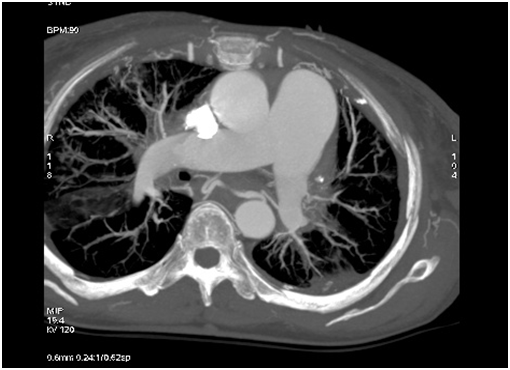

A 54 year-old woman who gave birth to two children, was followed in an outside hospital for a history of chronic dyspnea and asthenia. She presented to the emergency department several times for respiratory failure secondary to recurrent pulmonary infections since her childhood before she was referred to our department for complementary investigations. She presented with cyanotic lips, a pulse oximetry with 90% saturation, and audible wheezing without cardiac murmur at auscultation. Chest radiography showed bilateral diffuse interstitial lung syndrome. Pulmonary function tests revealed both restrictive and obstructive respiratory patterns. Thoracic computerized tomography (CT) demonstrated ground-glass opacities of the superior and inferior lobes of the right lung and the inferior lobe of the left lung with a small left hemithorax and left mediastinal shift. Results of lung biopsy support non-specific chronic inflammation. No abnormalities were found in laboratory tests including complete blood count, anti-DNA and antinuclear antibodies, anti-SSA, anti-SSB and Waaler-rose test. An electrocardiogram (ECG) and a transthoracic echocardiography (TTE) were performed to assess the impact of lung disease on cardiac structures and functions. Right bundle branch block was found on ECG. In TTE, pulmonary veins (PVs) were not seen except for the right inferior pulmonary vein (PV), right cardiac chambers were dilated without any valvular disease, cardiac defect or impaired ventricular function. To better delineate the anatomy, we choose to perform a cardiac CT with three-dimensional (3D) reconstruction in addition to cardiac catheterization. Cardiac CT highlights the absence of PVs except for the inferior right PV which was dilated and drained into the left atrium (Figure 1), left veinous return was provided by an important collateral blood flow and drained into the left atrium. The right pulmonary artery was dilated (Figure 2). Pulmonary hypertension, possible coexistent congenital heart disease and anatomy of anomalous venous return required cardiac catheterization including pulmonary angiography. Hemodynamic study showed a moderate pulmonary hypertension predominating on the left side. Blood gas analyses did not provide any signs of cardiac shunt. Venous angiography confirmed the cardiac CT findings.

Figure 1: Right PV with small left hemithorax. The right PV is dilated. Other PVs are atretic.

Figure 2: Dilated right pulmonary artery contrasting with small left pulmonary artery.

Cardiac CT scan confirmed the absence of left PVs and the upper right PV. The inferior right PV was dilated, probably to balance the upper one. The latter cardiac CT finding rectifies the TTE results. No connections to the left atrium in the expected site of insertion of the atretic PVs were observed, neither relics of PVs. Adult patients with such presentation may raise a diagnostic dilemma. One may argue that the absence of PVs may be an acquired anomaly secondary to a venous obstruction caused by thrombosis, mass lesion or fibrosis. Clinical history and laboratory tests do not provide other explanation of the lung fibrosis. The lack of bronchial or venous obstruction or any obstructive mediastinal mass in thoracic CT suggests a congenital origin. Thus magnetic resonance imaging was unnecessary to perform in the light of these results. Other abnormalities found in thoracic CT have been reported in other studies [15]. Since our patient was still alive and did not undergo surgery, pathological correlation was not available, which is a limitation of this report. Follow-up of patients with few or no symptoms [8,16] and selective embolization of systemic collaterals in cases of hemoptysis [4] are therapeutic options. Pneumonectomy guided by ventilation perfusion scintigraphy [13] may be suggested to inpatients with dyspnea, recurrent infections and to prevent pulmonary hypertension without significant left to right shunt [7,8]. Some authors support surgery as a first therapeutic option [7], others chose to delay it in adult symptomatic patients provided they were followed-up for development of pulmonary hypertension [8] which was our therapeutic choice.